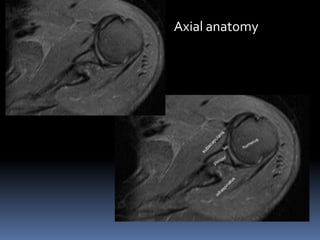

Axial anatomy